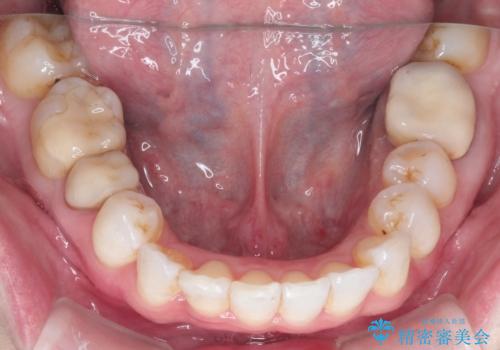

インビザラインによる非抜歯矯正 ガタガタな歯並びを整った歯並びへ

- 上下の全体的ながたつきが気になるとのことで来院されました。

全体的に歯と歯の間にわずかに隙間を作り、歯を並べました。